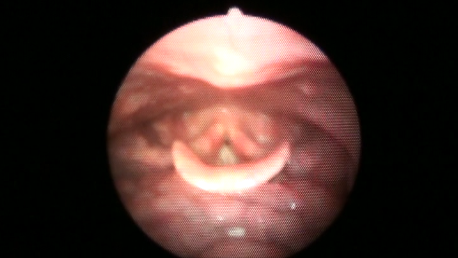

当院の訪問歯科診療では、内視鏡を使った、食物がきちんと飲み込めているかの検査や、アドバイスも実施しています。

年齢を重ねると、ものを噛んだり飲み込んだりする機能が段々と低下してしまうもの。

そこで、食事中にむせないようにしたり、スムーズに飲み込んだりできるようにするリハビリ・訓練がとても重要になるのです。

また、現在、死亡原因の第3位である肺炎は、高齢者が患う場合、唾液や食物が気管に入ってしまうことで引き起こされる「誤嚥性肺炎(ごえんせいはいえん)」がほとんどです。

正常に、安全に食事を取ることは、肺炎予防にもつながります。